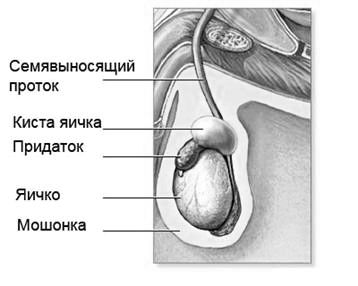

Кіста яєчок у чоловіків: причини, -